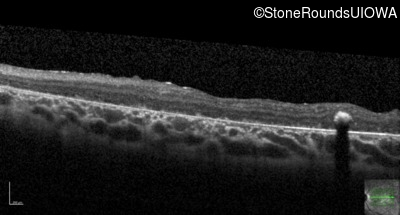

Optical Coherence Tomography - Left - 20/250 sc

Exemplar / OCT Stack